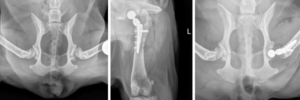

At Dallas Veterinary Surgical Center (DVSC), innovation and surgical excellence go hand in hand. Michael Orencole, DVM, DACVS recently performed his first Mini Cementless Total Hip Replacement (THR) using the KYON system, reimagining what’s possible for small patients like Izzy, a 9-year-old Corgi with severe hip dysplasia.

Historically, femoral head ostectomy (FHO) has been the standard for small breeds, but it often results in long-term gait abnormalities. The KYON Mini THR now offers a groundbreaking alternative, specifically designed for patients weighing 2–15 kg, with benefits including:

• Cementless fixation with immediate stability and long-term bone integration

• Preservation of bone structure, reducing trauma and recovery times

• Improved long-term function modeled after large-breed THR success

With Izzy’s successful surgery, DVSC joins a select group of hospitals worldwide equipped to perform this advanced procedure — another way Ethos hospitals are revolutionizing veterinary medicine through innovation.